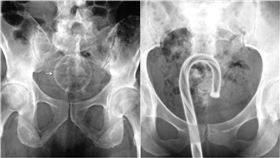

聖誕飾品成性玩具!她拐杖糖卡下體醫看傻

聖誕節即將來臨,各處充滿濃濃耶誕氣氛,然而英國一名女...

異物侵入身體…醫曝最慘器官是它!

美國政府近日指出,不少民眾會在自己體內塞進各式各樣的...